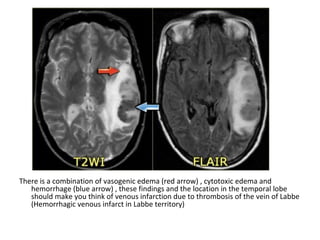

There is a combination of vasogenic edema (red arrow) , cytotoxic edema and

hemorrhage (blue arrow) , these findings and the location in the temporal lobe

should make you think of venous infarction due to thrombosis of the vein of Labbe

(Hemorrhagic venous infarct in Labbe territory)